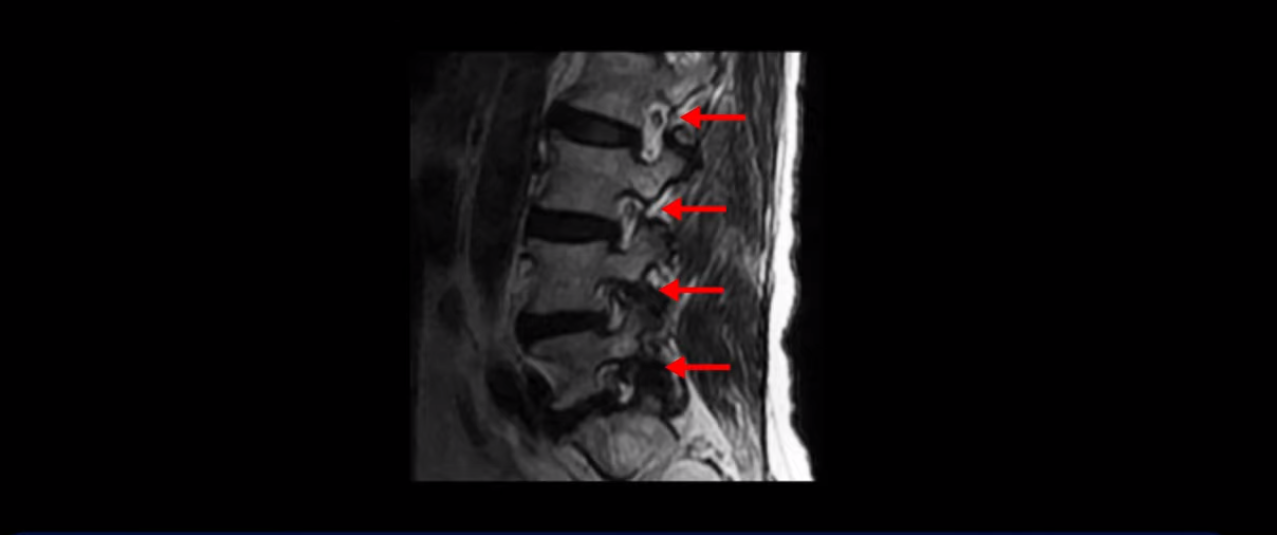

이분 MRI를 보시면 허리 세 마디가 퇴행은 있으나

척추관도 3번 4번

4번 5번

5번 1번

전부 다 충분히 넓고 왼쪽 다리 쪽으로 신경이 나가는 추간공도 전부 다 충분히 넓은 상태입니다.

신경이 눌려 보이지 않는 겁니다. 그러니까 수술 후 MRI를 보고 모든 병원이 전부 다 ‘수술은 잘돼 있다’, ‘아무것도 해줄 게 없다’ 그냥 기다리라고만 얘기했다고 합니다. 신경외과, 정형외과, 재활의학과가 서로 다른 과로 전과시키면서 다들 아무것도 해줄 게 없다고 하니 희망을 잃은 상태였다고 했습니다.